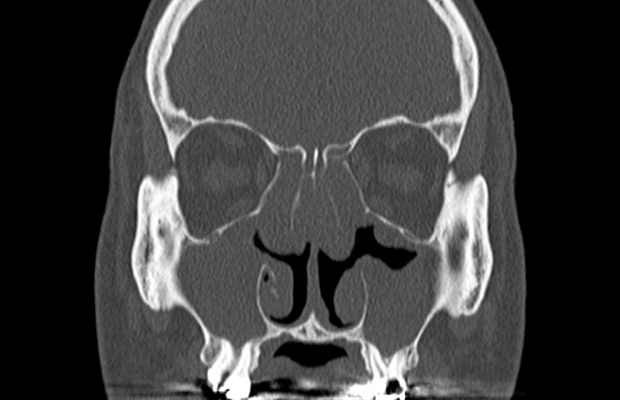

鼻腔内疾患診断支援システムの開発

難治性慢性副鼻腔炎に対する生物学的製剤の臨床効果の検討